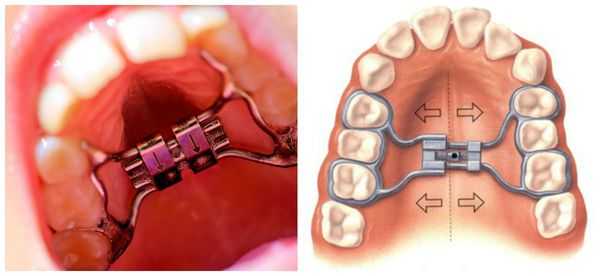

Для исправления прикуса используют съёмные и несъёмные ортодонтические пластинки из пластмассы с различными видами крепления (кламмеры, минивинты, ортодонтические кольца и коронки), а также другие конструкции с активными элементами (винтами и пружинами). Такие аппараты могут быть одночелюстными, двучелюстными и одночелюстными с межчелюстным действием.

Самая распространённая ортодонтическая аппаратура для исправления прикуса — брекет-системы. Для этого используются различные дополнительные приспособления: кнопки и крючки, эластики и эластичные цепочки.

Срок лечения брекет-системами в среднем составляет 15-18 месяцев и проводится в обязательном порядке на двух челюстях с последующим ношением ретейнера (шины) не менее 1,5 сроков активного периода лечения.

- расширение или сдерживание зубной дуги: в зависимости от состояния челюсти;

- устранение аномалии переднего отдела;

- вытягивание нижней челюсти кпереди;

- исправление нарушений в высоте окклюзии.